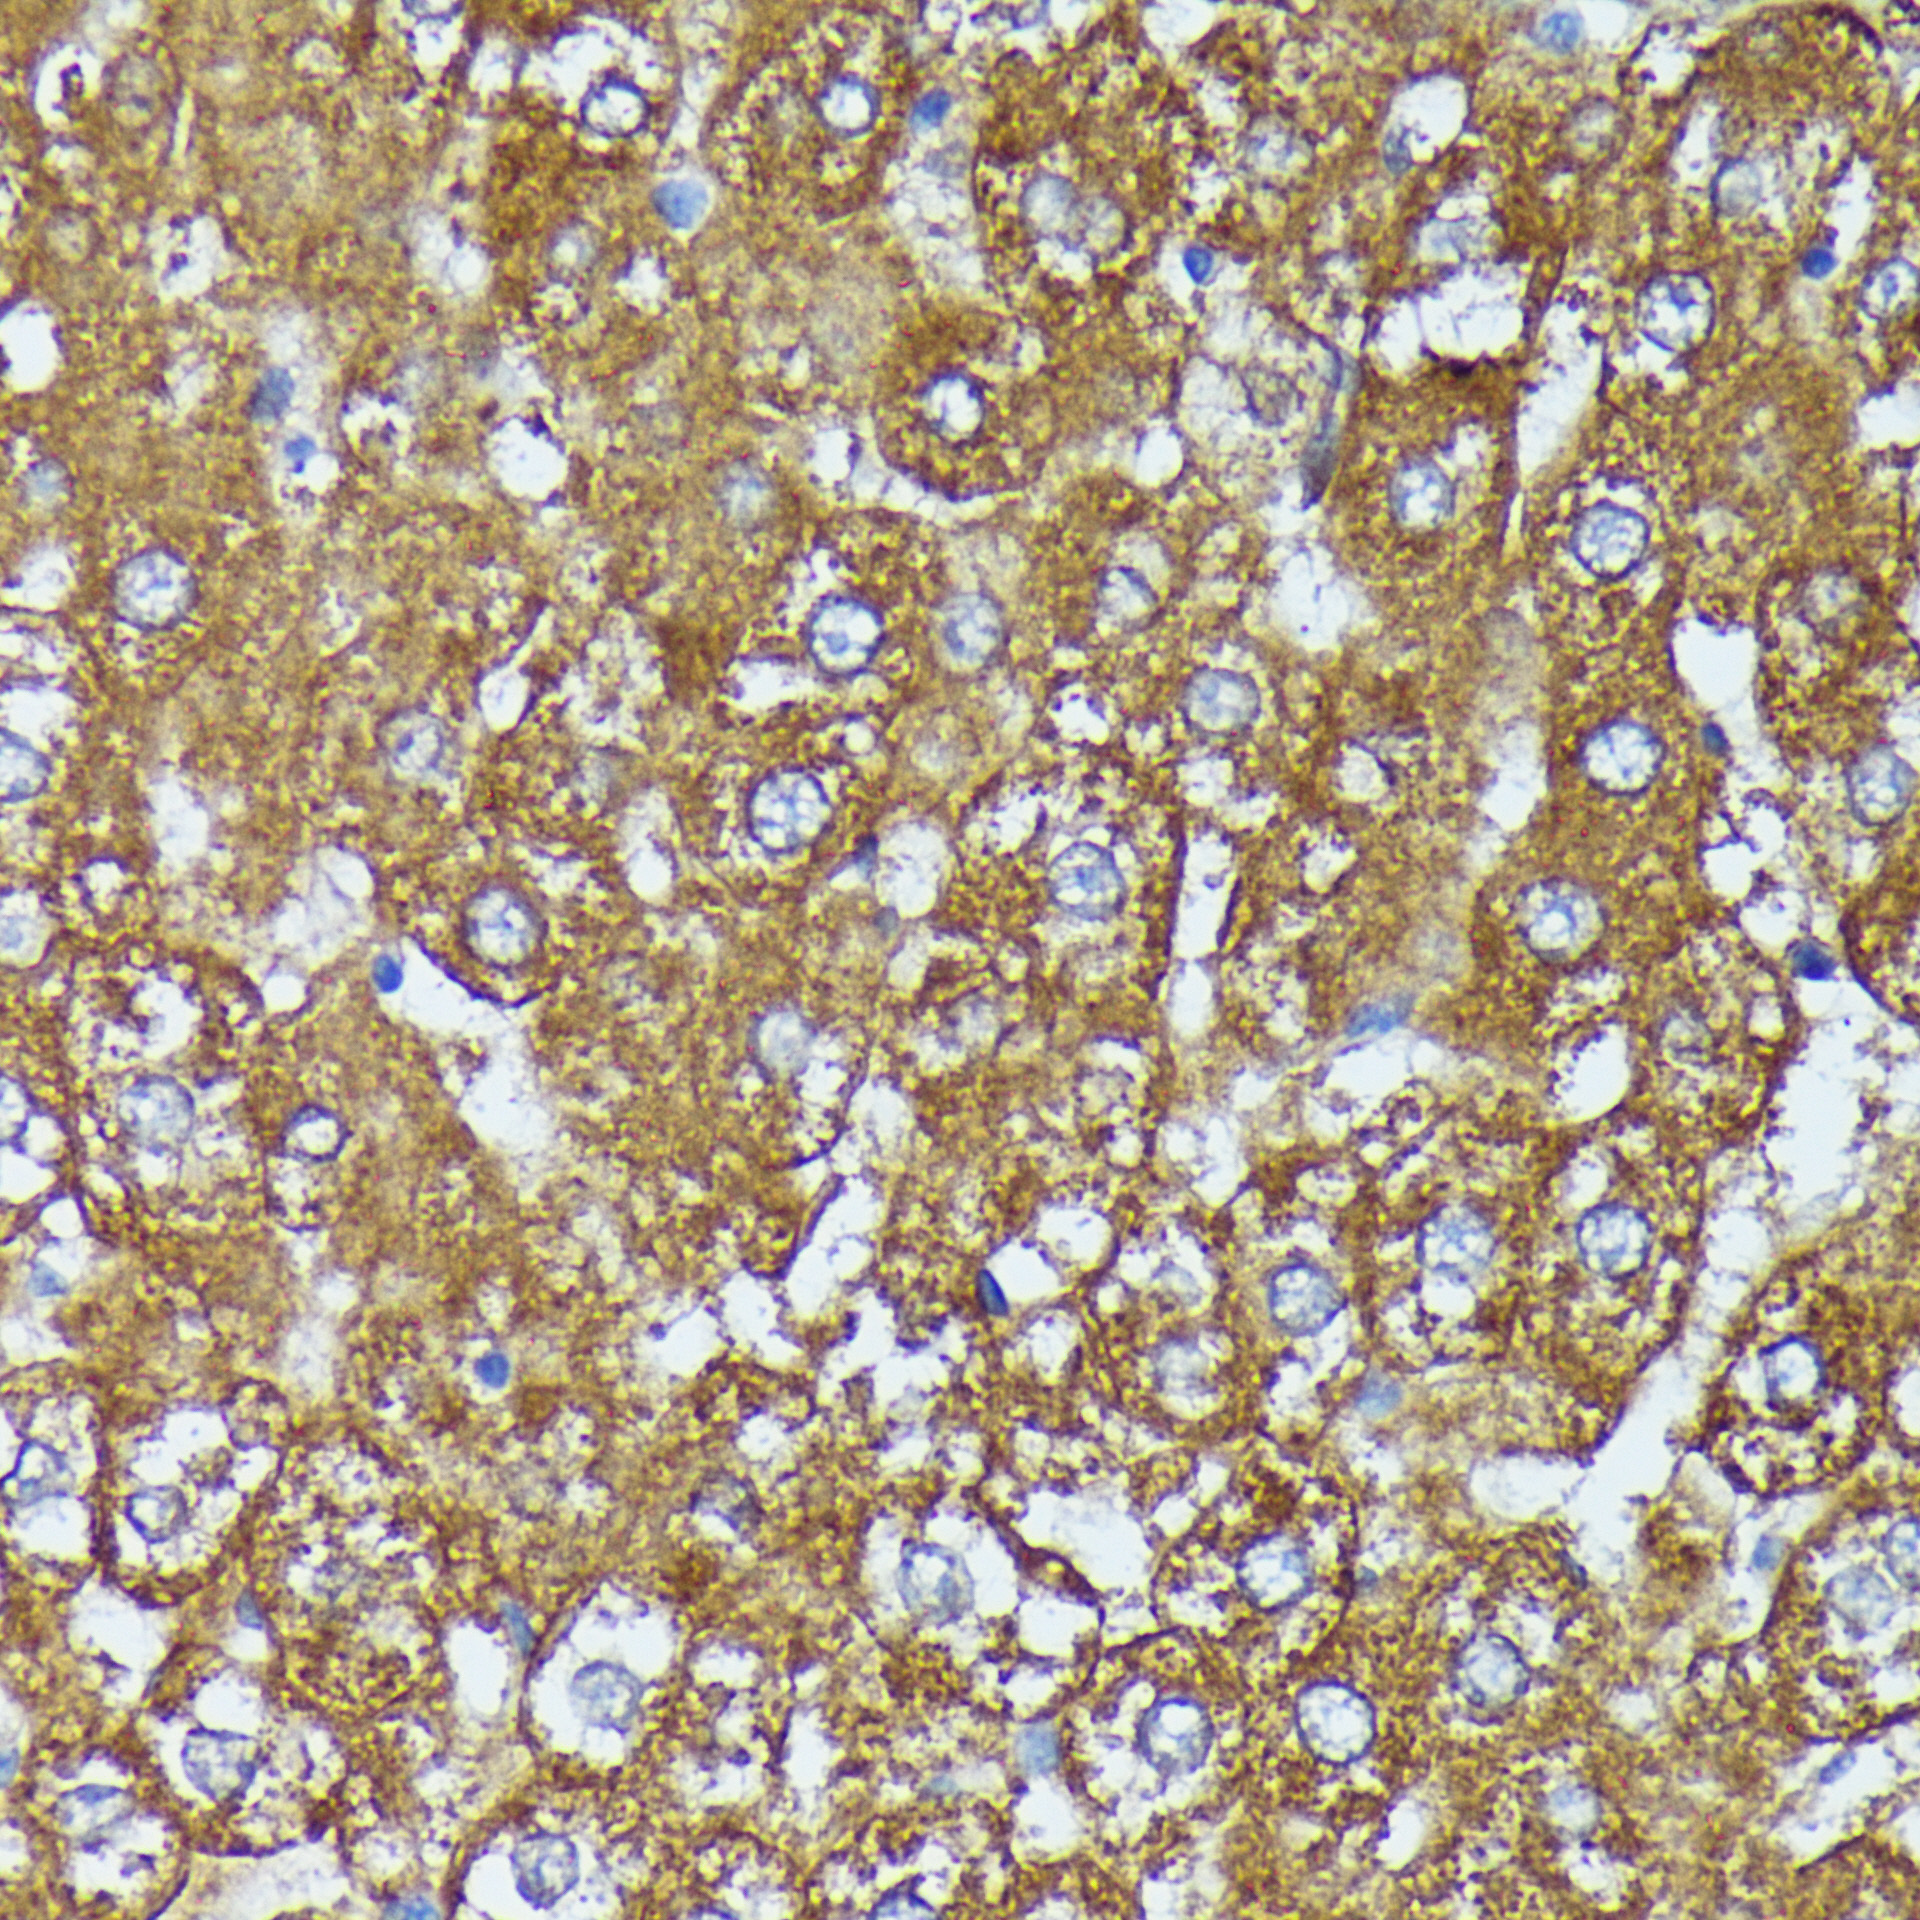

Immunohistochemistry of paraffin-embedded rat liver using AKR1C2 Rabbit pAb.

Immunohistochemistry of paraffin-embedded human liver cancer using AKR1C2 Rabbit pAb.

Immunohistochemistry of paraffin-embedded human Colon cancer using AKR1C2 Rabbit pAb.

Immunohistochemistry of paraffin-embedded mouse liver using AKR1C2 Rabbit pAb.